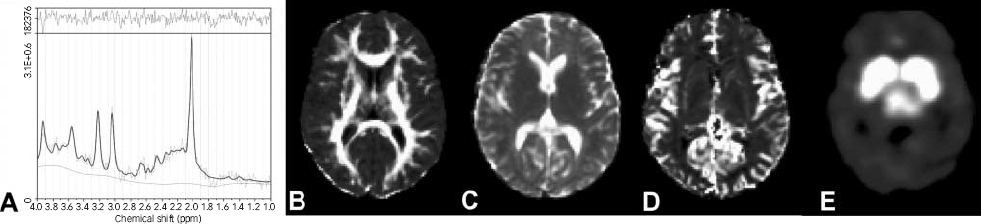

Apparent diffusion coefficient and fractional anisotropy maps were calculated from the diffusion tensor imaging Reference Hunsche, Moseley, Stoeter and Hedehus13 and cerebral blood volume maps from the perfusion-weighted imaging scans. Fractional anisotropy, apparent diffusion coefficient and cerebral blood volume were spatially normalised by registration to the Montreal Neurological Institute brain template (MNI152), and segmentation was performed to separate into cerebral spinal fluid, white and grey matter (Fig. 1). The cerebral blood volume maps were intensity-scaled to mean individual cerebral blood volume intensity of white matter derived from the segmentation procedure to generate relative cerebral blood volume maps.

Fig. 1 Representative images of an individual (a) 1H-magnetic resonance spectroscopy after analysis by Linear Combination of Model spectra and representative (b) fractional anisotropy; (c) apparent diffusion coefficient; (d) regional relative cerebral blood volume; and (e) [123I]β-CIT binding images after transformation to the spatially normalised Montreal Neurological Institute brain template.

Attenuation correction of all images was performed as previously described. Reference de Win, Habraken, Reneman, van den Brink, den Heeten and Booij14 Images were reconstructed in 3D mode (www.neurophysics.com). All SPECT scans were registered (rigid body) to the T1-3D MRI scans of the same participant using a software package developed for 3D and 4D registration of multiple scans for radiotherapy application. Reference Wolthaus, van Herk, Muller, Belderbos, Lebesque, de Bois, Rossi and Damen15 Next, the same program was used to register the individual MRI scans to the MNI152 brain using affine transformations. For both registration steps an algorithm was used that maximises mutual information of the voxels of the scans to be registered. Reference Maes, Collignon, Vandermeulen, Marchal and Suetens16 Finally, the software package was used to resample the individual SPECT images to the MNI152 brain (Fig. 1), resulting in 91×109×92 voxel images with voxel sizes of 2×2×2mm3. In this way, all SPECT images could be analysed together.